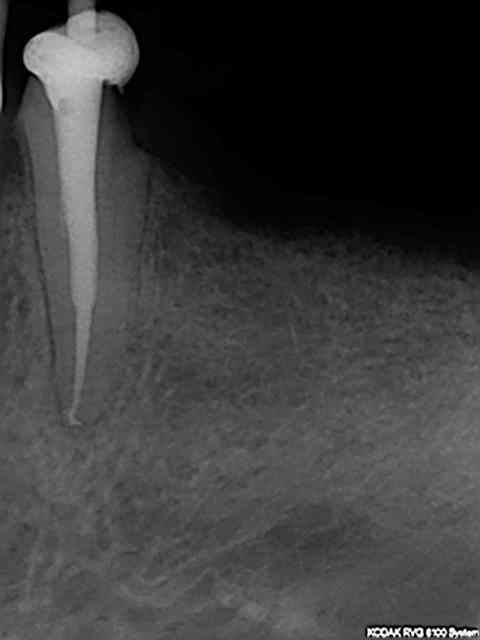

alapex

" pour être sur d'être à l'apex "